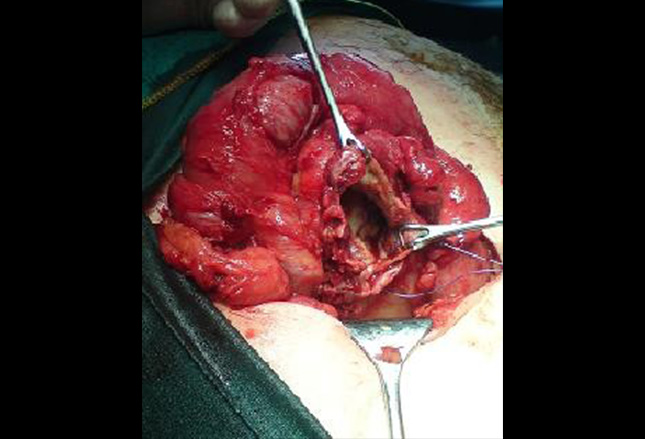

术中图像显示在盲肠底部较大的阑尾穿孔。